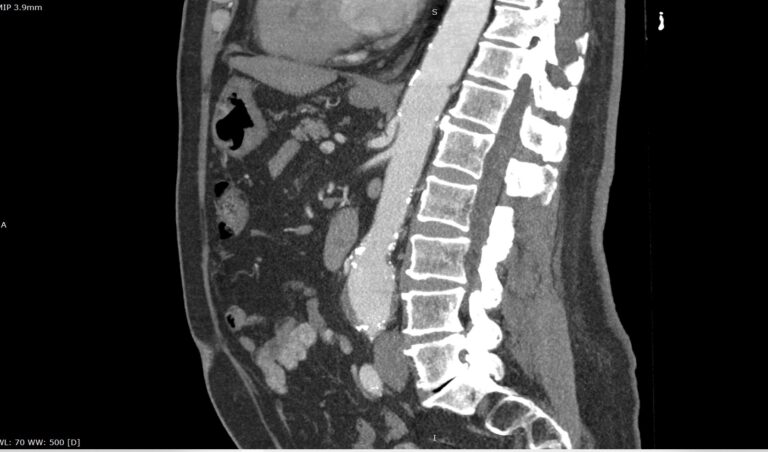

При возникновении подозрения на стеноз чревного ствола за счет экстравазальной компрессии при синдроме Данбара исследование проводится с функциональными пробами, на вдохе и на выдохе для уточнения зависимости степени сужения от фазы дыхания. При выполнении функциональных проб также возможно определить сдавление правой почечной артерии или левой почечной вены.

Мультиспиральная компьютерная томография с внутривенным болюсным контрастированием является быстрым, безопасным и неинвазивным (то есть не требующий вмешательства в организм пациента) способом диагностики патологии чревного ствола. Метод основан на использовании ионизирующего излучения и способности тканей поглощать рентгеновские лучи.

В диагностических центрах «Доступная медицина» КТ чревного ствола выполняется на современных мультиспиральных компьютерных томографах экспертного класса TOSHIBA AQUILION. Аппараты послойно сканируют исследуемую область с шагом от 0,5 мм, при этом для улучшения визуализации сосудистого русла в вену пациента вводится йодсодержащий контрастный препарат.

Контраст хорошо поглощает рентгеновские лучи, что обеспечивает высокую контрастность изображений брюшной аорты и висцеральных ветвей на снимках. С помощью инновационных цифровых приложений данные, полученные при сканировании, реконструируются в трехмерные изображения сосудистой системы. Методика обеспечивает точную и достоверную диагностику стенозов чревного ствола, при этом современные технологии, применяемые при сканировании, сводят к минимуму лучевую нагрузку на пациента.

На снимках мультиспиральной компьютерной томографии с контрастированием хорошо визуализируется брюшная часть аорты, чревный ствол, брыжеечные артерии. При этом можно выявить признаки поражения висцеральных ветвей аорты, то есть сужение просвета сосудов за счет: